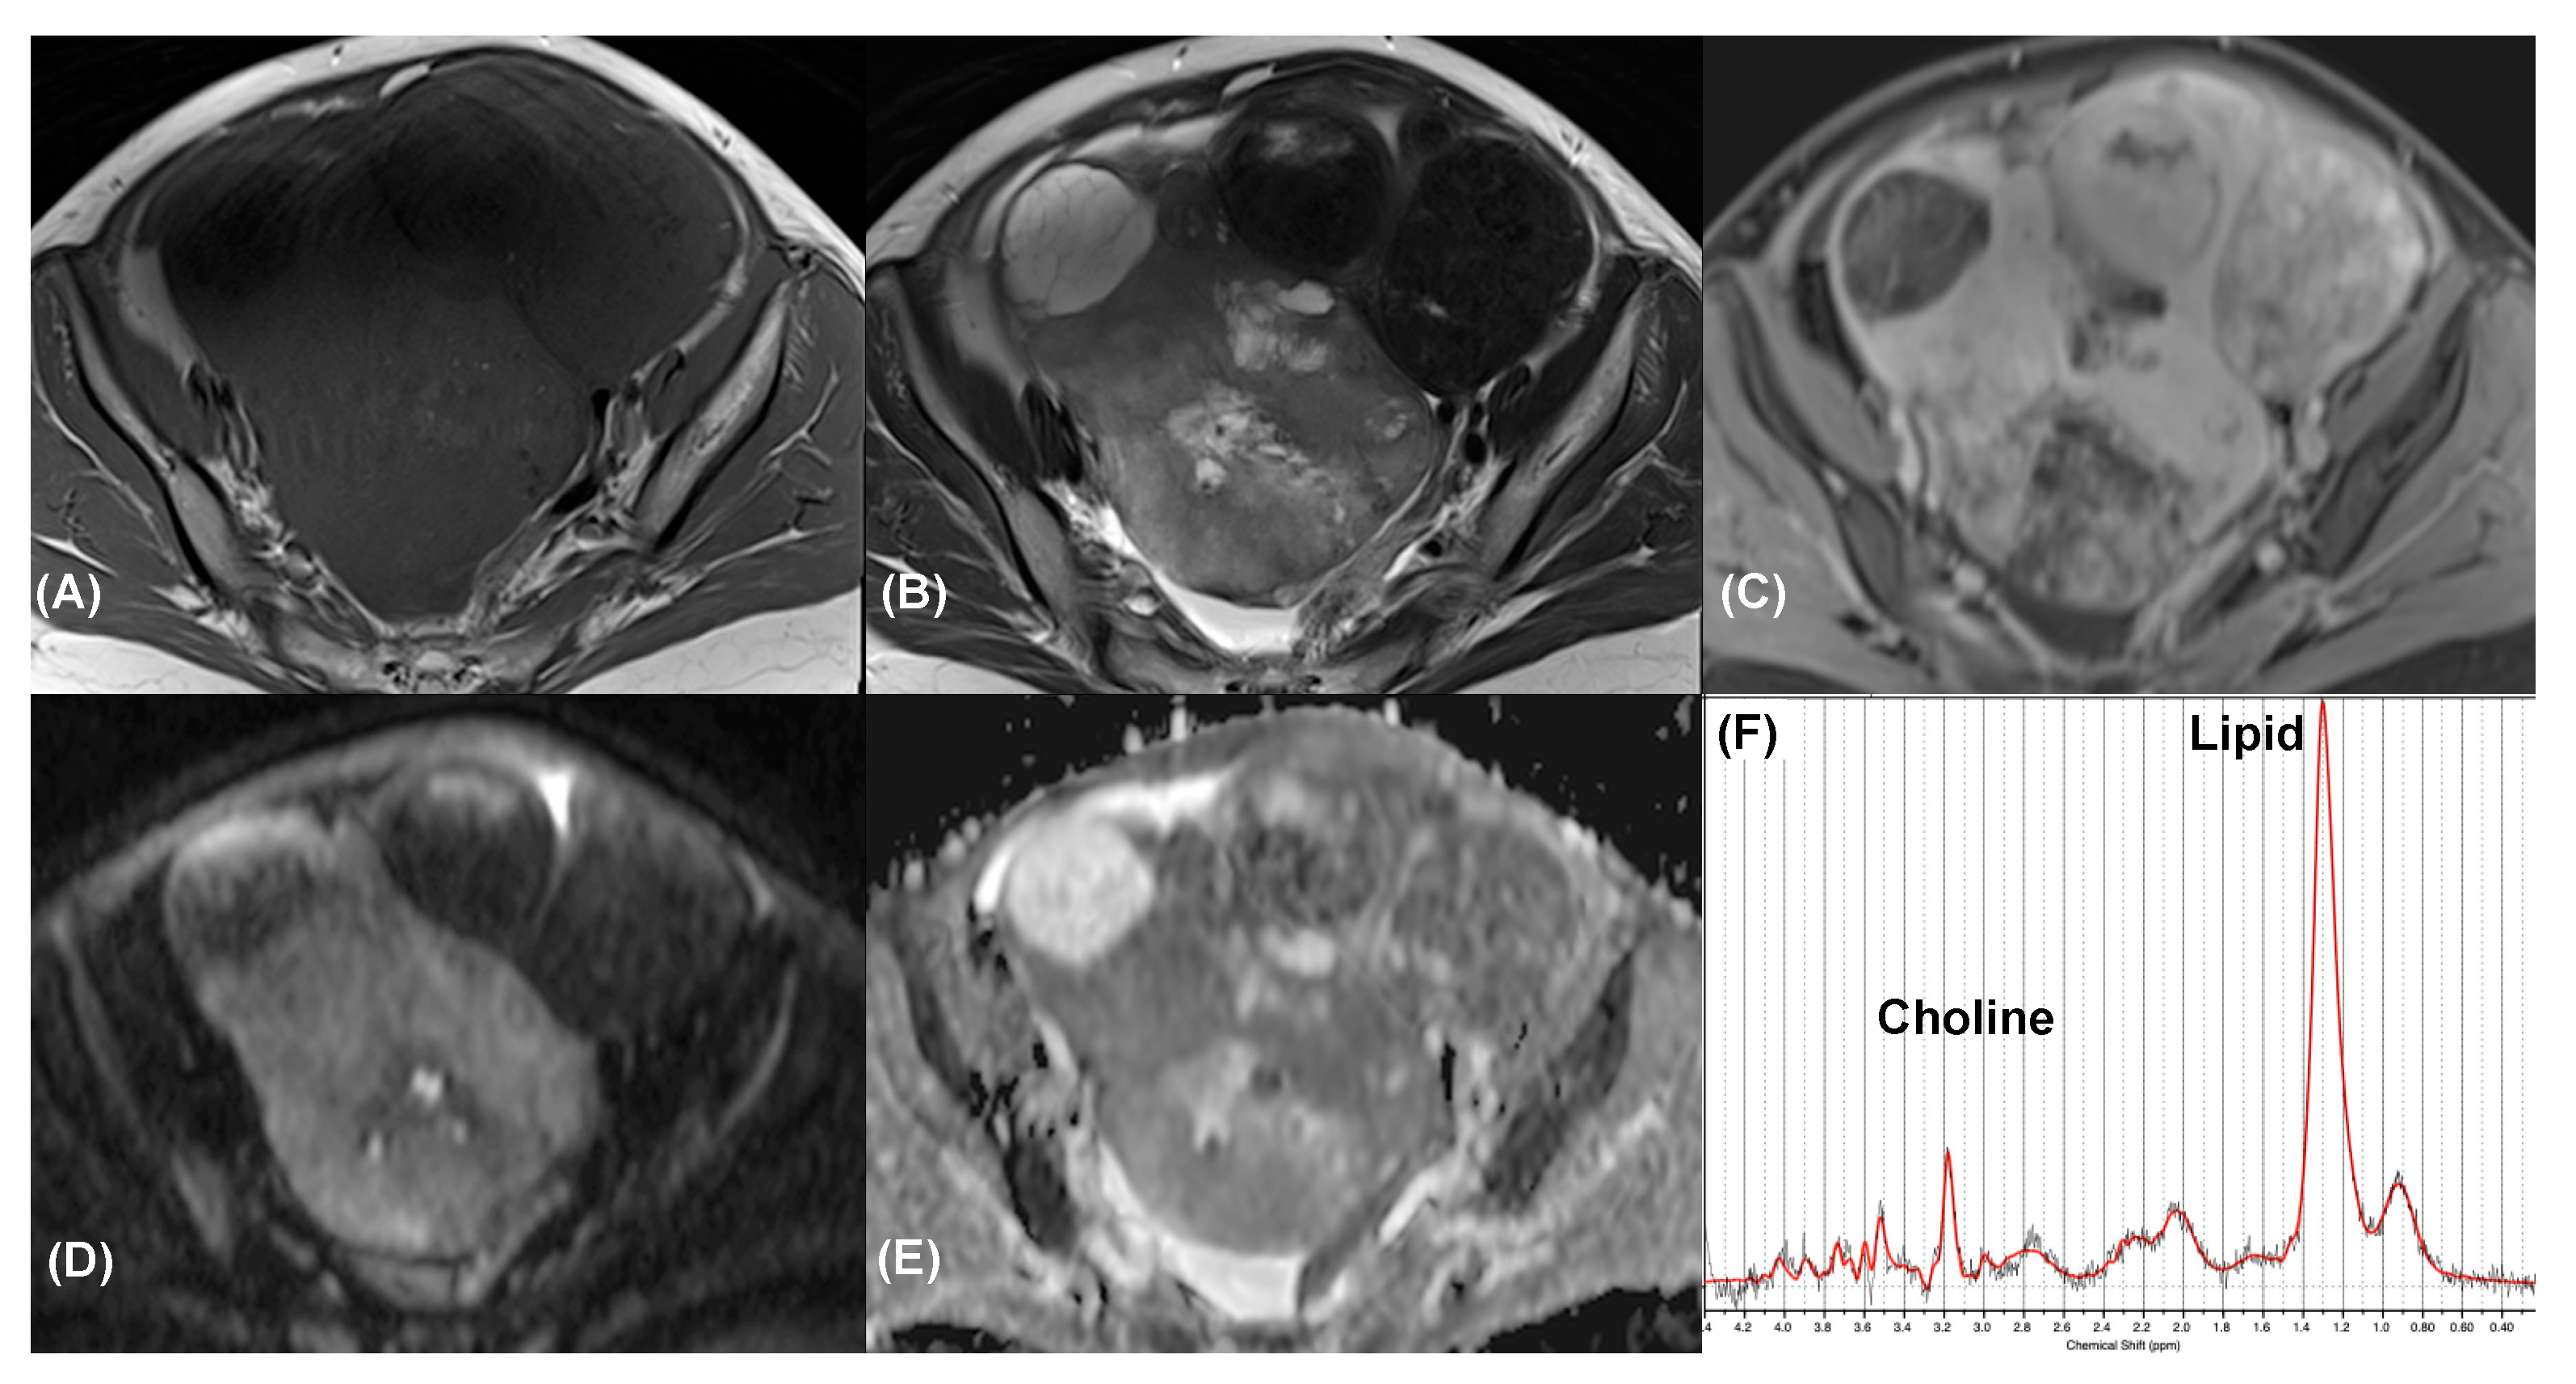

Figure 4.

Clear cell carcinoma in a 33-year-old woman. Axial (A) T1-weighted, (B) T2-weighted, and (C) contrast-enhanced T1-weighted MR images show a cystic tumor in adnexa with irregular solid component (arrow) exhibit marked contrast enhancement. Axial (D) high-b-value DW image (b = 1000 s/mm2) and (E) ADC map demonstrated marked restricted diffusion of the solid component. The tumor was classified as an O-RADS 5 lesion. (F) MR spectroscopy depicts choline and lipid peaks (SNR = 29.0 ± 1.8; linewidth = 4.7 ± 1.2 Hz). Data are in black, and the corresponding fit is in red.